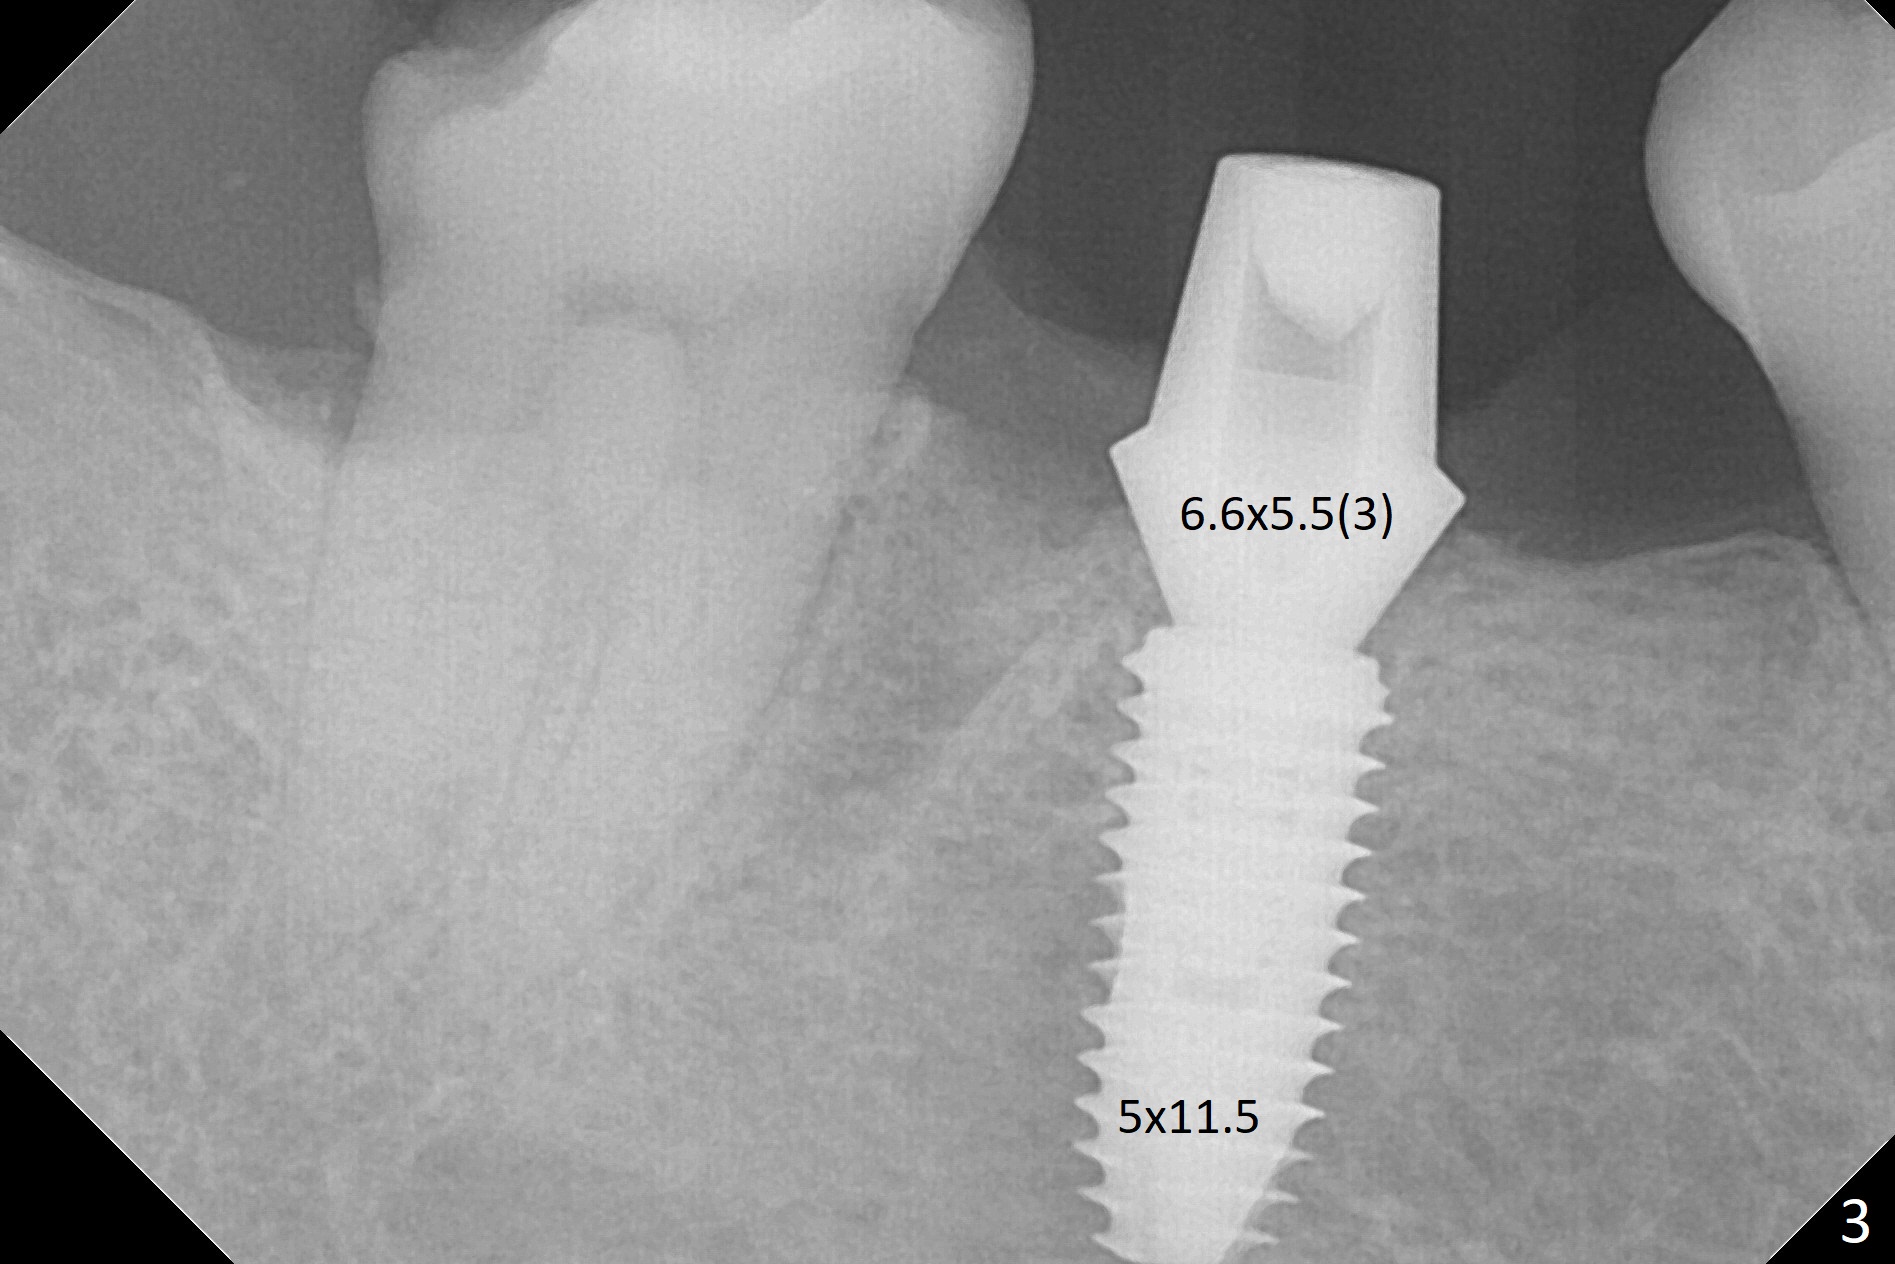

Because of severe pain, block anesthesia is administered prior to extraction. The mesial socket of the tooth #30 is deep with granulation tissue. A 4.5x10 mm dummy implant is placed with < 40 Ncm following sequential osteotomy until 4x13 mm over the septum (Fig.1 (low density)). After 4.5x13 mm drill, a 5x10 mm dummy implant is inserted with <40 Ncm (Fig.2). Since the Inferior Alveolar Canal is invisible (Fig.1,2 (pan should have been taken)), a 5x11.5 mm implant is placed with <20 Ncm. When a 6.5x5.5(3) mm abutment is placed, the underlying implant is turned (Fig.3). With collagen plug is placed in the distal socket and Vera graft around the implant, an immediate provisional is fabricated and relined. When it is seated, it has mobility. In fact the provisional should be locked into the edentulous area while it is malleable. To prevent low primary stability, osteotomy should be under prep, since the implant (red circle) contacts only two bony surfaces, i.e., the mesial (M) and distal (D) walls of the mesial socket (Fig.4 (occlusal view) black oval). There are gaps buccally (B) and lingually (L). In case of low stability, a healing screw or abutment should be placed; the remaining socket is closed with suture. The provisional is loose 19 days postop; it is removed by sectioning. A healing screw is placed. Twelve days later, the wound heals (Fig.5). The patient returns for uncover 8 months postop; although the implant has osteointegrated apparently, the crestal bone resorbs to the implant plateau level (Fig.6 arrow). It seems that the immediate implant should be routinely placed 2-3 mm deeper. The open margin is closed with composite when the abutment/crown is removed after cementation (Fig.7).